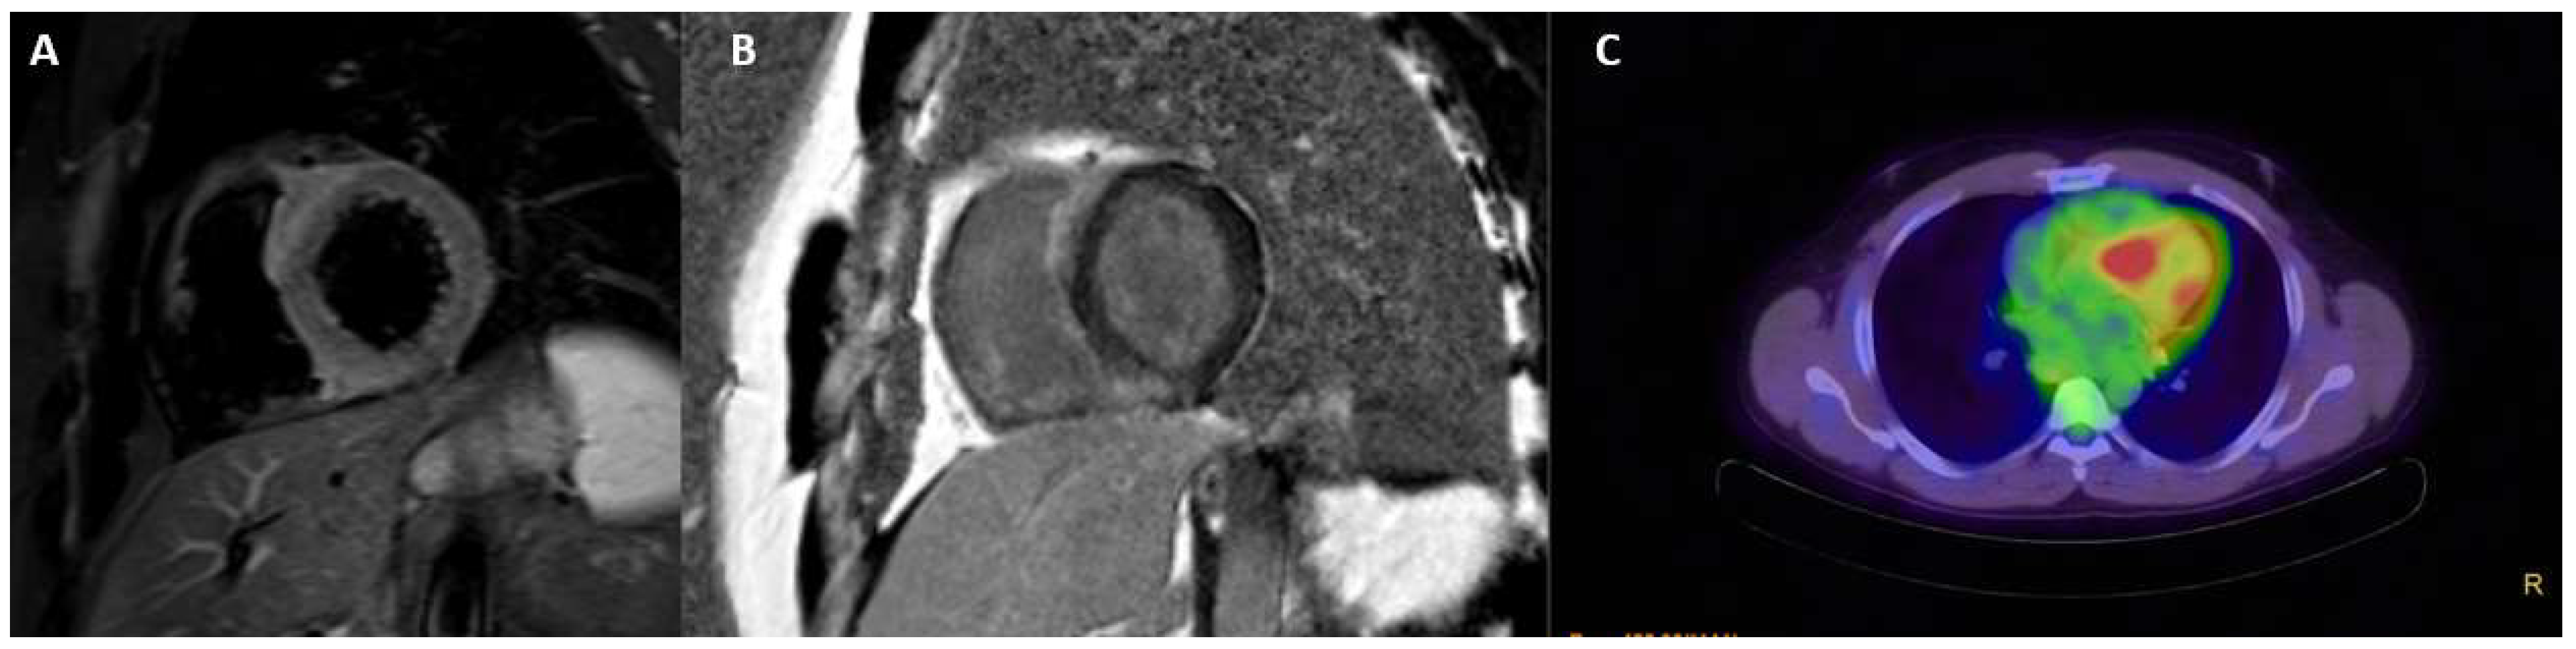

3.7. Cardiac Sarcoidosis

- Slart, R.H.J.A.; Glaudemans, A.W.J.M.; Lancellotti, P.; Hyafil, F.; Blankstein, R.; Schwartz, R.G.; Jaber, W.A.; Russell, R.; Gimelli, A.; Rouzet, F.; et al. Document Reading Group. A joint procedural position statement on imaging in cardiac sarcoidosis: From the Cardiovascular and Inflammation & Infection Committees of the European Association of Nuclear Medicine, the European Association of Cardiovascular Imaging, and the American Society of Nuclear Cardiology. J. Nucl. Cardiol. 2018, 25, 298–319. [Google Scholar] [CrossRef]